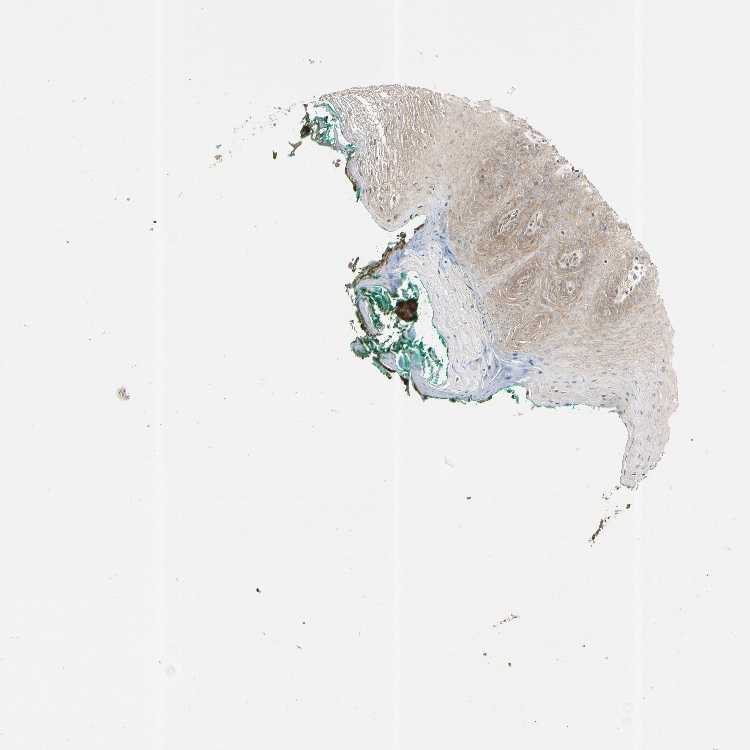

TISSUE PRIMARY DATA ORAL MUCOSA Show tissue menu

ORAL MUCOSA - Antibody stainingi

Antibody staining in the annotated cell types in the current human tissue is reported as not detected, low, medium, or high, based on conventional immunohistochemistry profiling in selected tissues. This score is based on the combination of the staining intensity and fraction of stained cells.

Each image is clickable and will lead to virtual microscopy that enables deeper exploration of all samples and also displays staining intensity scores, fraction scores and subcellular localization as well as patient and tissue information for each sample.

Antibody CAB009729

Squamous epithelial cells Low